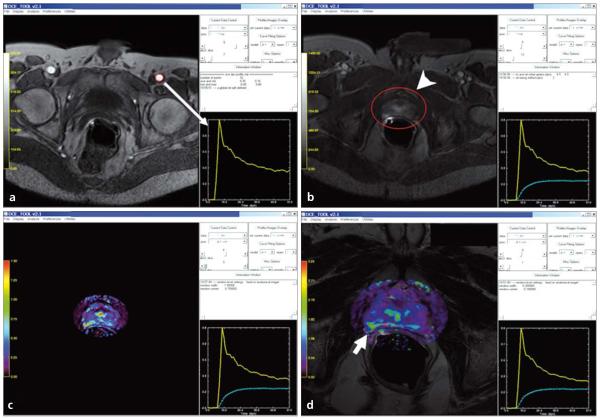

a–d. Screen captures of quantitative analysis of prostate DCE-MRI on DCE-Tool (Philips Healthcare, Cleveland, Ohio, USA). First, an arterial input function (yellow graph) is defined by using the left femoral artery (red circle) (arrow) (a); secondly, a tumor region of interest containing tumor is selected (arrowhead) and a contrast uptake delay time is calculated (dashed green graph) (b); then kinetic parameter maps are obtained (c), which can be overlaid with T2W images (d): overlaid color-coded Ktrans map and T2W image delineates the tumor lesion located at the right peripheral zone of the prostate (short arrow, d).